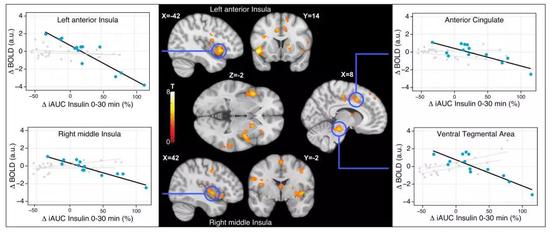

結果是代糖組和真糖組,對糖的耐受量(敏感度)沒啥區別,但是混合組對糖的(敏感度)下降了。有fMRI(功能性磁共振成像)對混合組成員的大腦的掃描為證,相關味覺區域的耗氧量有變化:

雖然通過對三組人員的問訊發現,他們對甜味的需求口感主觀變化不大,但fMRI掃描照片則證明混合組潛在的糖需求會變大。